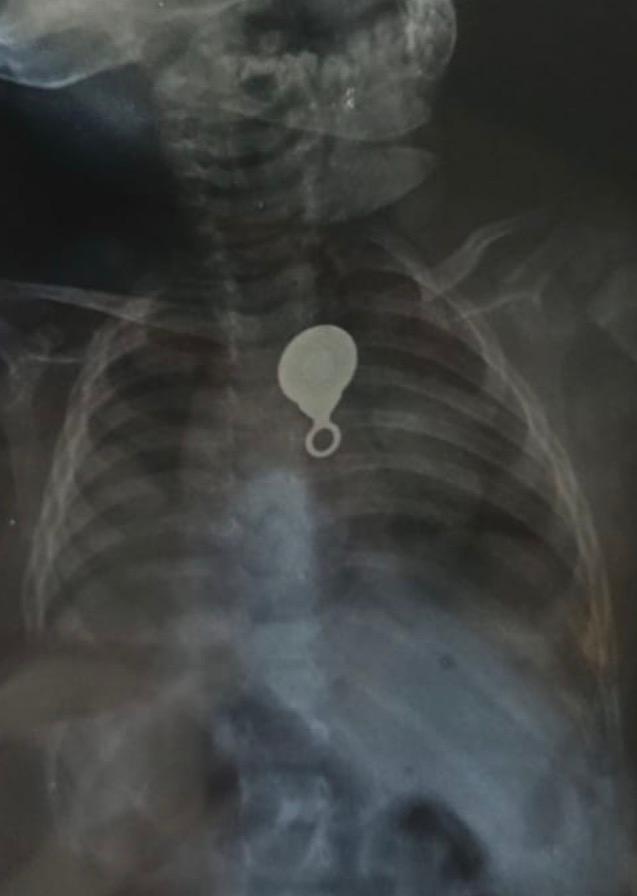

وأوضح بيان الوزارة، أن الطفلة كانت قد حضرت إلى قسم الاستقبال والطوارئ بالمستشفى وهي تعاني من قيء مستمر منذ نحو أسبوع، وبفحصها بواسطة طبيب مقيم الأطفال، تم إجراء أشعة عادية على الصدر أظهرت وجود جسم معدني داخل المرئ، تبيّن لاحقًا أنه "سوستة شنطة" كانت قد ابتلعتها الطفلة دون علم أسرتها.

وأضاف البيان أن الحالة استدعت على الفور استدعاء فريق مناظير الجهاز الهضمي للأطفال، حيث تم تجهيز الطفلة لإجراء منظار علوي طارئ، نجح من خلاله الفريق الطبي في استخراج الجسم الغريب بأمان كامل وبدون أي مضاعفات.